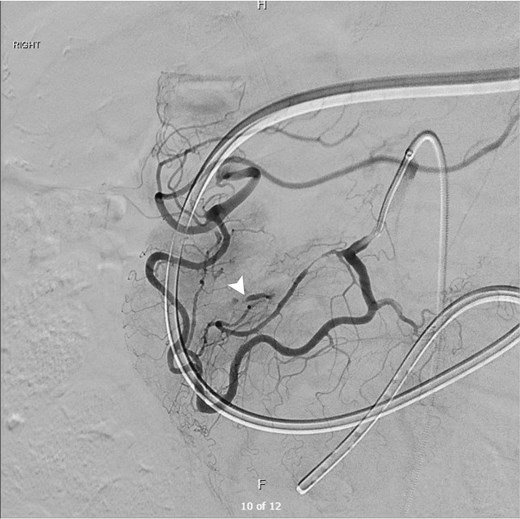

The patient underwent catheter angiography, confirming the presence of the aneurysm within the collateral pathway (Fig. 3). He underwent successful transcatheter embolization of the pancreaticoduodenal aneurysm. His post-procedural recovery was uneventful, and his obstructive symptoms resolved over a course of 2 weeks as the hematoma burden decreased. Ultrasound Doppler of mesenteric vessels showed more than 75% coeliac axis stenosis proximally. He is currently under surveillance by the vascular outpatient clinic with three yearly CT angiography for recurrence of aneurysms/pseudoaneurysms and would consider for elective celiac axis stenting if recurs.

Digital subtraction angiogram demonstrating the hypertrophied pancreaticoduodenal arcade providing collateral retrograde flow from the SMA to the celiac territory. A distinct aneurysm (white arrowhead) is visualized arising from the collateral pathway, confirming the diagnosis.